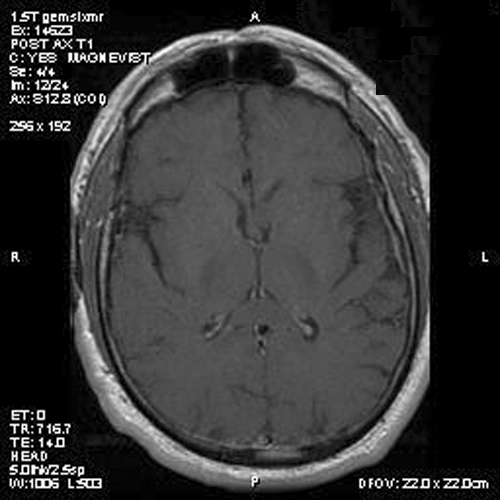

Panel A is T1-weighted post contrast MR image, Panel B is a SPGR T1-weighted post contrast MR image and Panel C is FSE T2-weighted image. Panel D and E are taken from cytologic preparation from intraoperative consultation. Panel F to H are taken from frozen sections. Panel I to L are taken from paraffin section.

Image of the case: In the left frontal horn there is a well demarcated, subependymal mass measuring approximately 1.1 x 0.5 cm which is relatively hyperintense to white matter on T1-weighted image (Panel A and B) as well as T2-weighted image (Panel C) sequences. It does not enhance on the post contrast images. There is no obstruction of the foramen of Monro.

Typically, subependymoma occur as a fungating mass that protrudes into the ventricle. A mild to sometime significant hydrocephalus can be caused by these tumors. On T1-weighted images, they have intensity similar to that of the surrounding white matter. T2-weighted images usually do not demonstrate significant edema around these tumors. Some of its properties also varies according to the locations. In tumors arising in the fourth ventricle, calcification and heterogeneous contrast enhancement are common; whereas these findings are rare in subependymomas arising in the lateral ventricles 6.